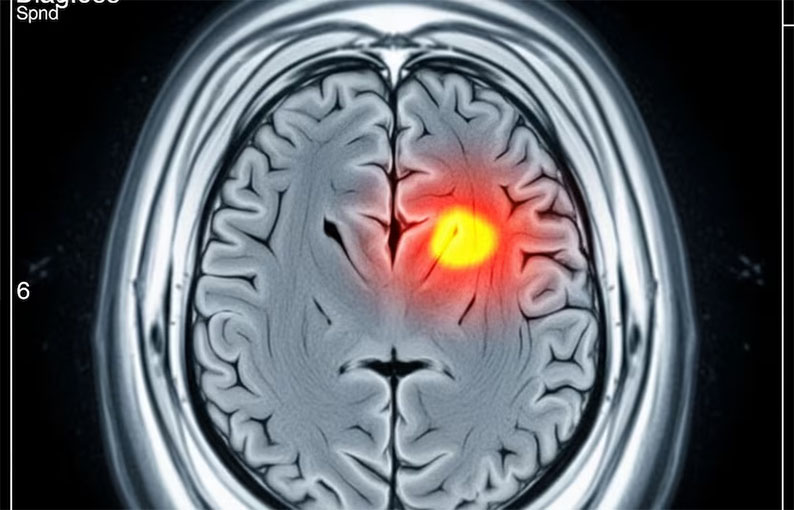

Un metaanálisis realizado por la Universidad de Cambridge reveló que el consumo de drogas psicoactivas, como anfetaminas, cocaína y cannabis, puede más que duplicar el riesgo de sufrir un accidente cerebrovascular.

El estudio se basa en el análisis de datos médicos de más de 100 millones de personas y aporta nuevas pruebas sobre la relación causal entre el consumo de estas sustancias y el riesgo de accidente cerebrovascular, una de las principales causas de muerte y discapacidad en el mundo.

El análisis, encabezado por el equipo del Departamento de Neurociencias Clínicas de la Universidad de Cambridge, identificó que los consumidores de anfetaminas presentan un riesgo 122% mayor de accidente cerebrovascular, mientras que quienes consumen cocaína enfrentan un aumento del 96%.

El cannabis, aunque con un impacto menor, eleva el riesgo en un 37%.

El riesgo se incrementa aún más en menores de 55 años: en este grupo, el consumo de anfetaminas casi triplica la probabilidad de sufrir un accidente cerebrovascular, el cannabis la aumenta en un 14% y la cocaína mantiene un riesgo del 97% superior respecto a quienes no consumen esas sustancias.